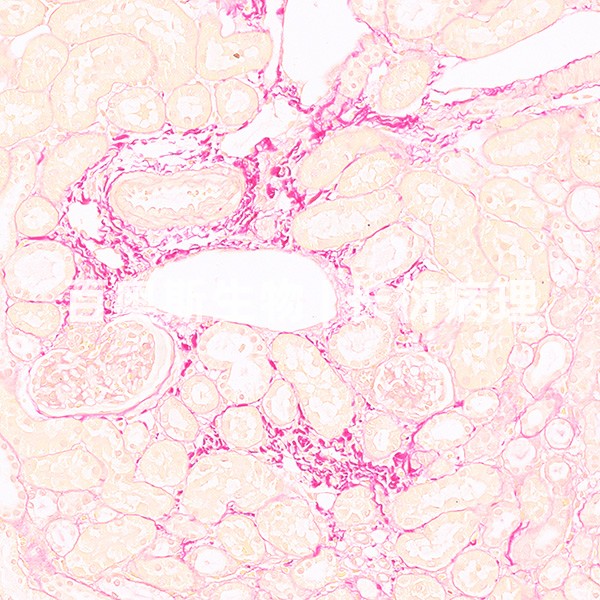

组织病理学实验

油红O染色